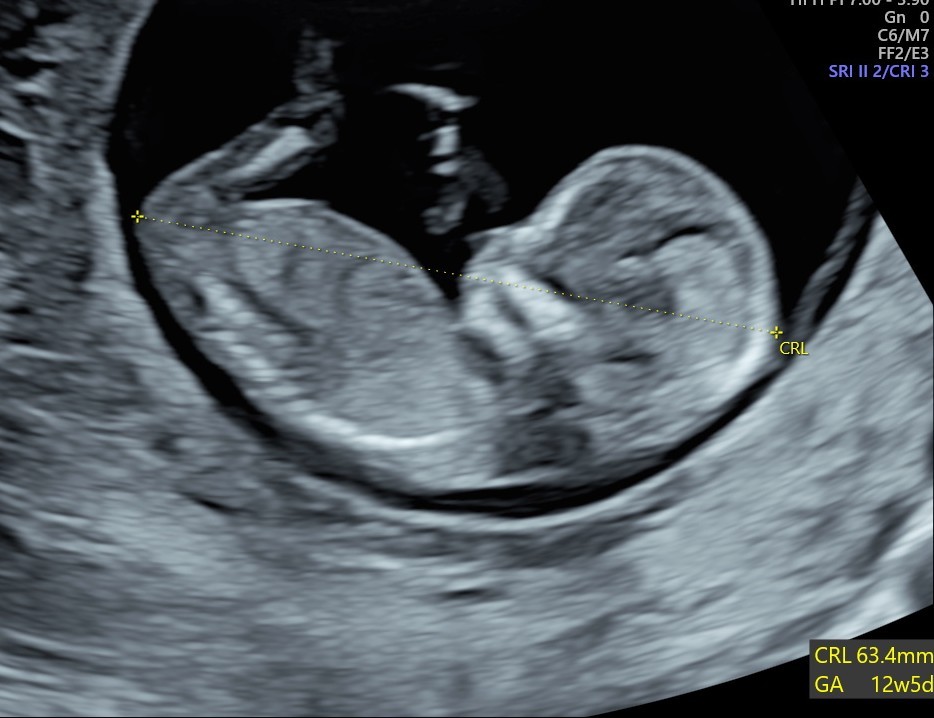

What do you see on an early pregnancy scan?

A gestation sac with a yolk sac and a foetal pole (baby) with a heart beat. We can measure the foetal pole to date the baby.